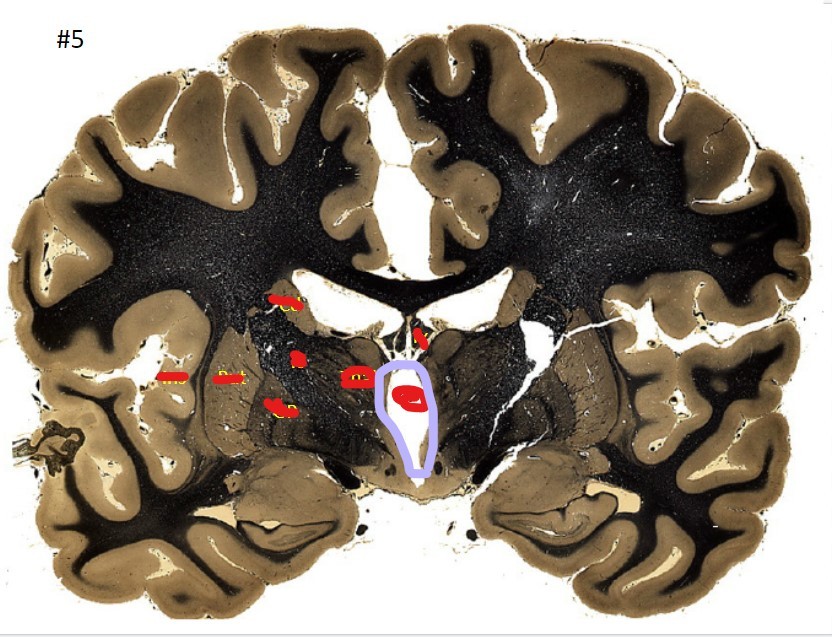

what is the circled area (#5)?

the caudate nucleus

the 3rd ventricle

the globus pallidus

the internal capsule

the putamen

the amygdala

the beginning of the hippocampus